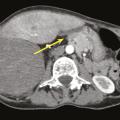

Traitements médicaux des sarcomes osseux, des sarcomes des tissus mous et des GIST

Les molécules utilisées dans le traitement médical des sarcomes diffèrent selon le type d’atteinte, la localisation et la phase concernée. La question des traitements d’entretien reste ouverte.